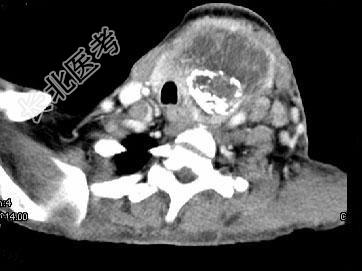

- 单项选择题女,64岁, 发现双甲状腺肿大1个月余,CT如图所示, 最可能的诊断是 ( )

A、结节性甲状腺肿

B、甲状腺腺瘤

C、甲状腺癌并淋巴结转移

D、甲状腺转移瘤

E、甲状腺结核